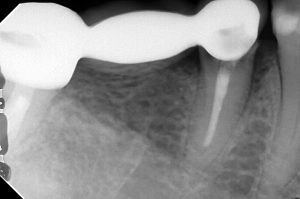

埋入時のレントゲン。

この状態で2~3カ月待ち、